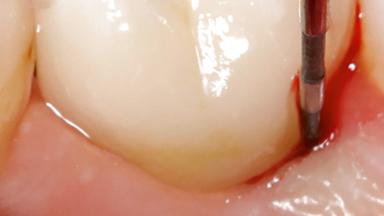

Treatment of Peri-Implantitis at a Zirconia Implant

Due to their promising clinical performance, zirconia implants have recently become popular alternatives to titanium implants, particularly for areas with high esthetic demands (Holländer and coworkers 2016; Roehling and coworkers 2016; Lorenz and coworkers 2019). However, regardless of the reported high survival and success rates, zirconia implants were affected by peri-implant diseases over the short observation period, suggesting the importance of treating peri-implant diseases at zirconia implants (Becker and coworkers 2017). In their case, Frank Schwarz and Ausra Ramanauskaite present 3-year results following mechanical debridement alongside Er:YAG laser monotherapy.